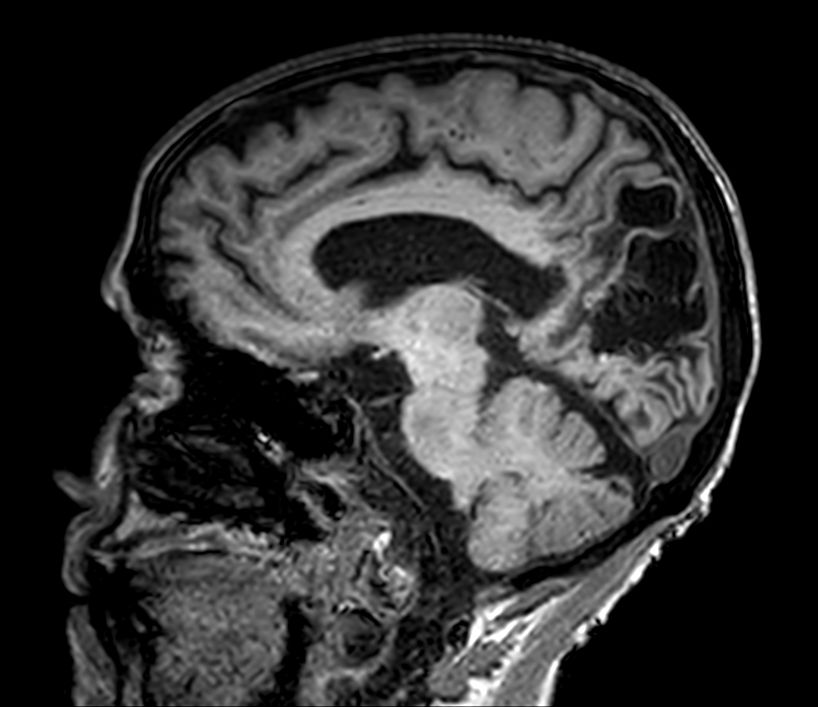

Sagittal 3D VIEW - T2w FLAIR

3D VIEW - T2w FLAIR (axial reformat)